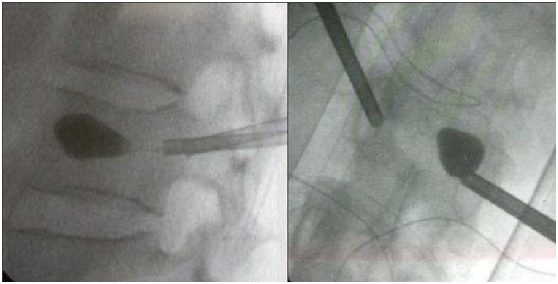

建立球囊通道

使用钻子开通道。

侧位相钻子直至椎体前中1/2交界处,正位钻头尖位于椎弓根影与棘突连线中点。

钻子必须出外鞘前端2cm,保证球囊完全进入椎体。

侧位像钻头尖在距椎体前缘2mm处停止正位显示钻头尖位于棘突边缘。